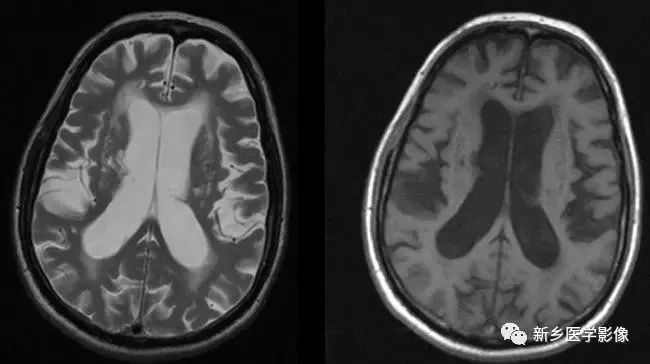

❽ 胼胝体发育不良

胼胝体发育不良可单独发病,但更常见的是伴有中枢伸经系统的其他畸形,包括胼胝体周围脂肪瘤、脑膨出、交通性脑积水、Chaiar-II畸形、Dandy-Walker囊肿、脑裂畸形等。

临床上可无症状或仅有轻度临床症状,临床检查可见眼距过宽、大头畸形、智力发育迟滞等。

胼胝体缺失时,MR冠状位上侧脑室前角呈新月形表现,侧脑室体部分离,呈垂直状平行走行。